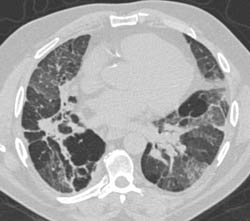

Diagnosis

Lipoma of the Left Supraclavicular Zone